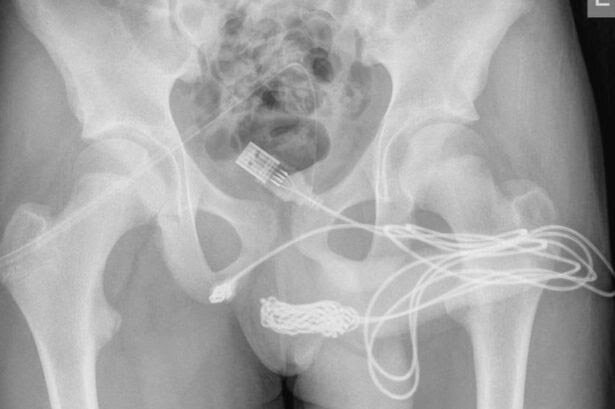

Поняв, что без операции тут не обойтись, юношу отправили на рентген.

И лишь после того как точная длинна и расположения кабеля стали им известны, хирурги аккуратно разрезали мышцы в районе мошонки подростка, а затем разорвали и извлекли от туда кабель.